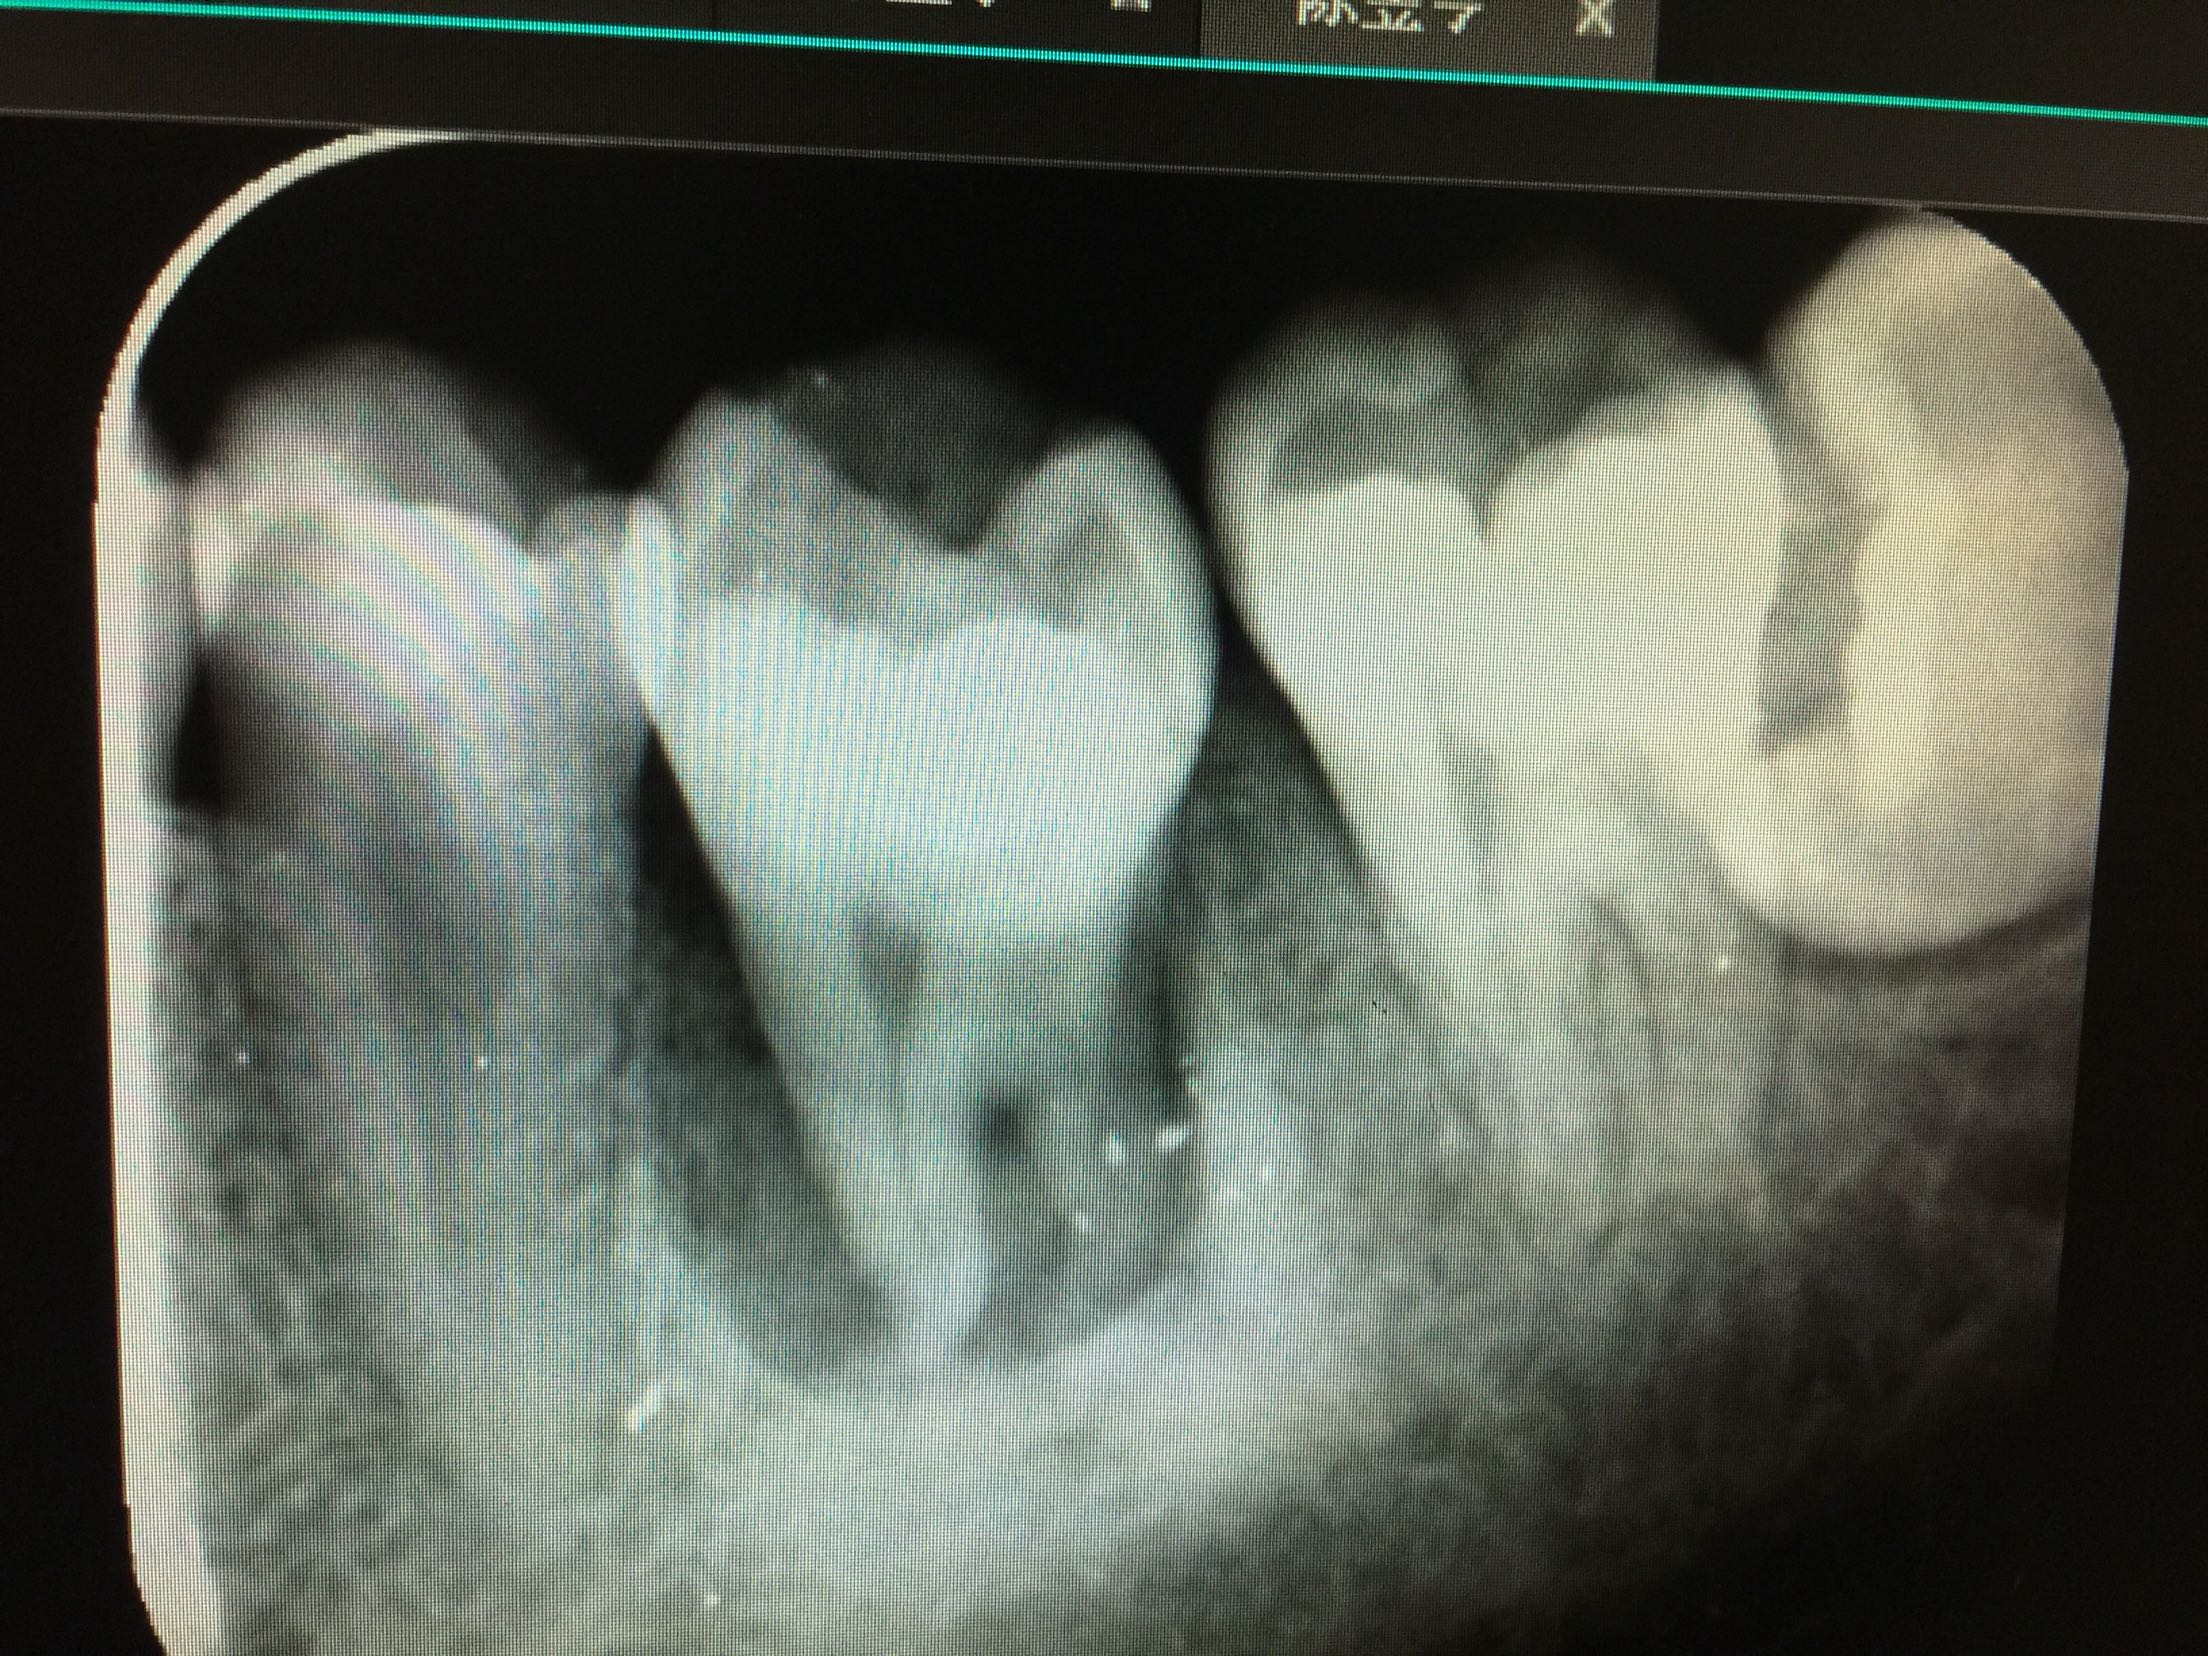

检查:全口卫生好,牙石+,软垢+,牙龈正常,无退缩。36牙远中邻合面龋,内有大量软龋,深达牙本质深层,已累及髓室底,冷-,探-,叩++,松+-。 X线:14牙颊合面可见龋坏,累及髓室底,未行根管治疗,根尖区有暗影。38牙近中阻生。

诊断:36根尖周炎 治疗计划:36牙拔除后行自体牙移植 治疗:拔除36牙后两周行自体牙移植(48牙),抗感染治疗,两周后复诊。

碧蓝麻局部浸润,36(48)牙开髓揭髓顶,探查根管3根,牙髓摘除术,k挫初步预备,根管测长仪测量根管长度,各根管内导入根管润滑剂EDTA,Protaper镊钛器械预备根管,冲洗,超声荡洗,水溶性氢氧化钙充填根管,暂封,约复诊。 复诊:一周后,诊间无不适,36牙暂封完好,冷-,探-,叩-,不松。 试主尖

根充